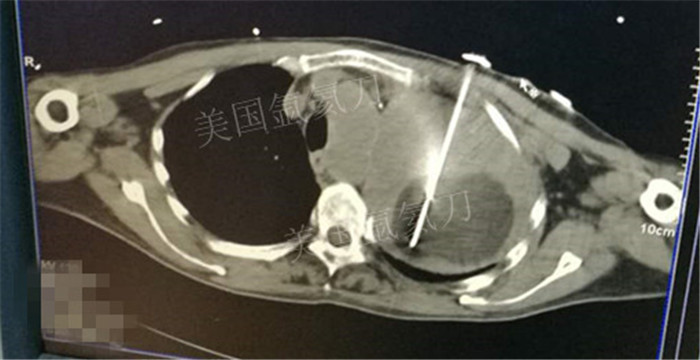

下一篇:氩氦冷冻治疗最大径8.2肿瘤,冰球最大径7.9